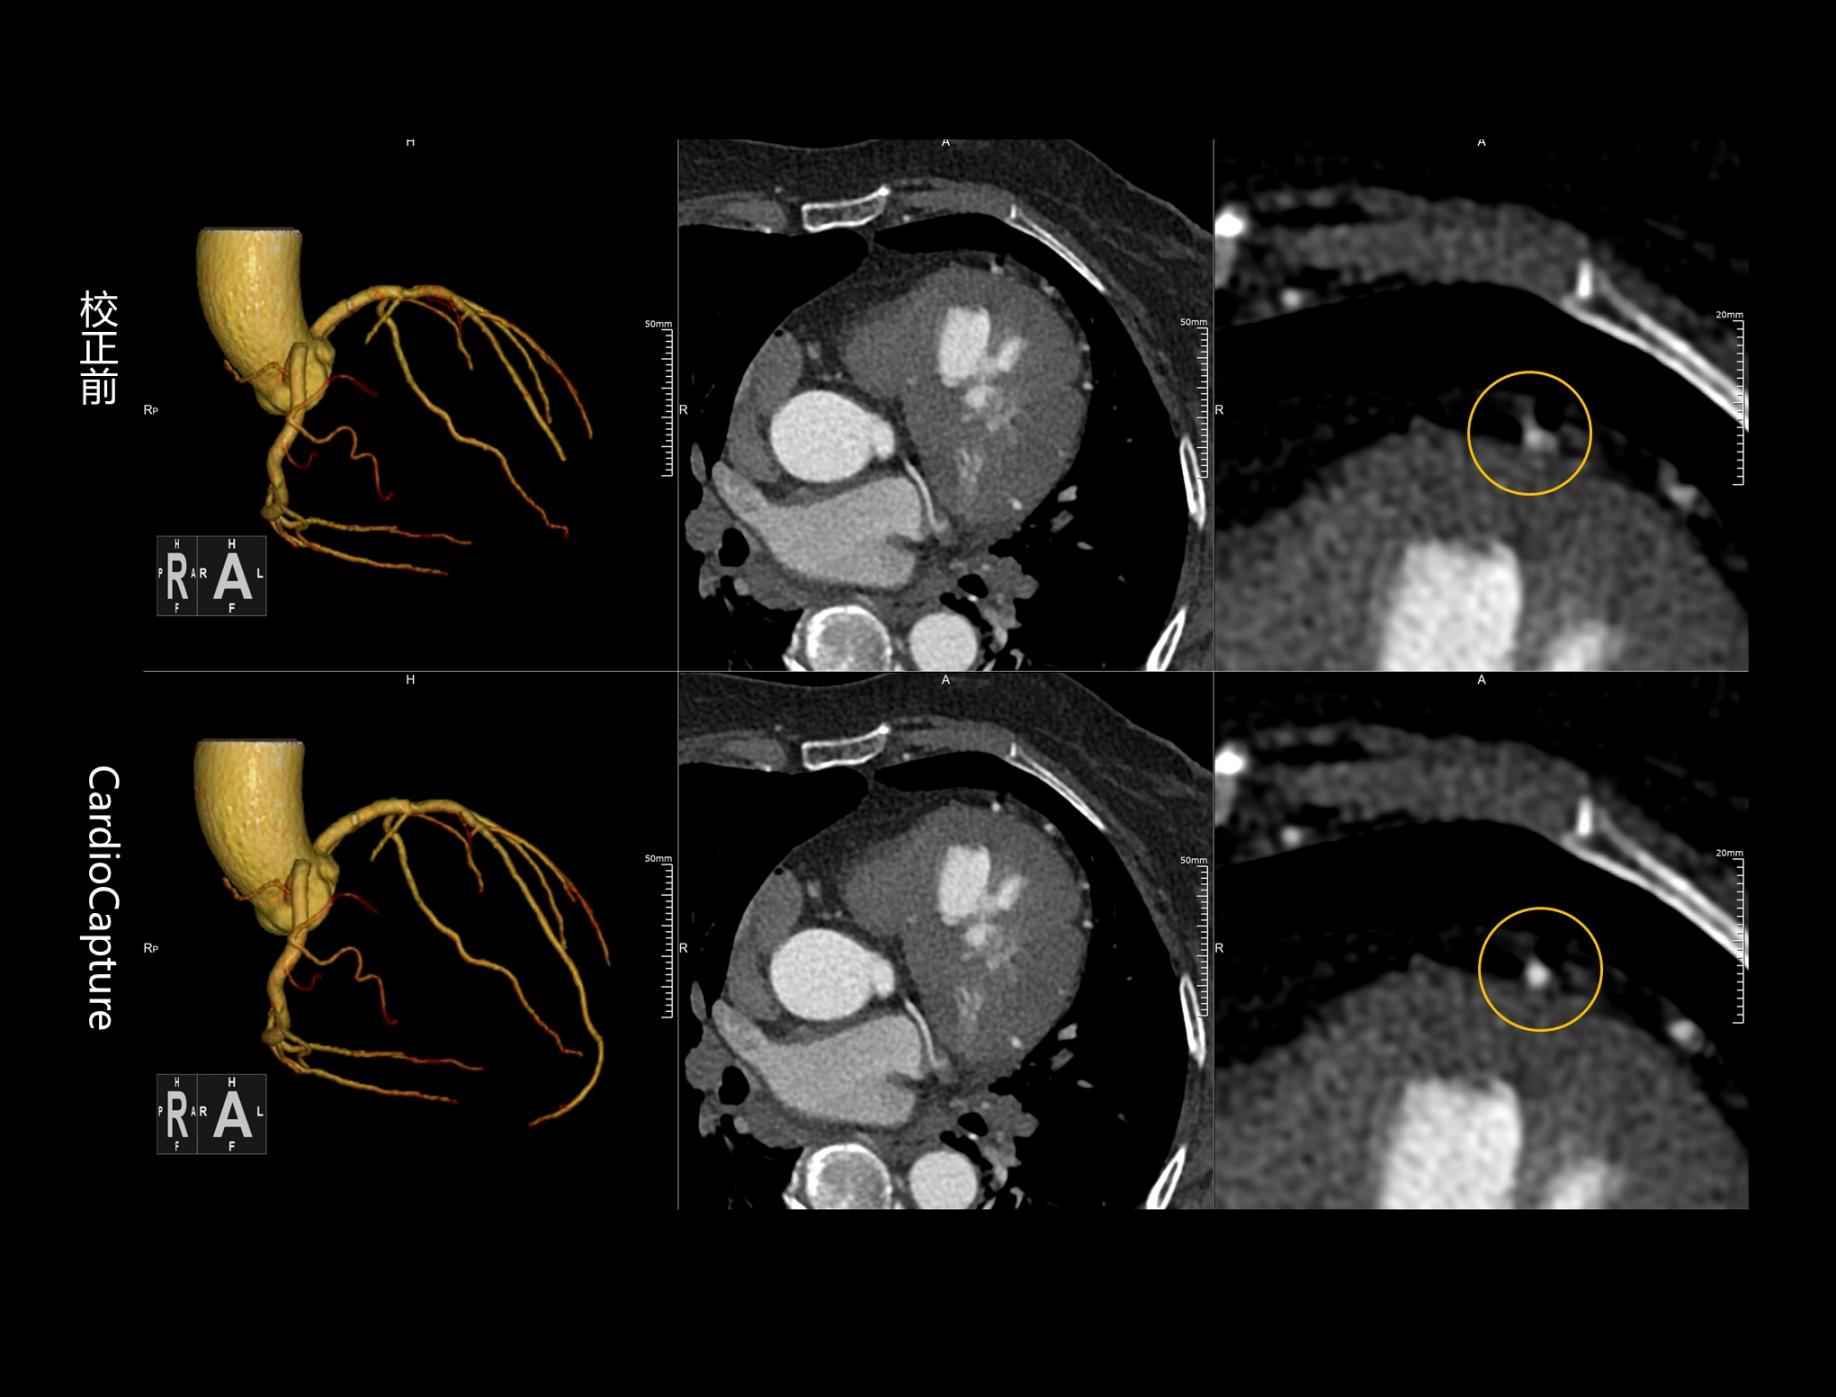

CardioCapture 冠脉追焦技术

AI深度学习冠脉中心线提取

CardioCapture AI冠脉追焦技术基于深度学习网络,充分学习各类冠脉图像,以适应不同冠脉场景,精准高效完成冠脉及中心线提取,相较于仅基于CT值和固定解剖模型的传统算法,CardioCapture对于小血管及末端血管显示优势更加显著。

超高时间分辨率

CardioCapture算法采用多时相数据重建,构建更加精细化的冠脉运动向量场,有效提升冠脉运动评估精准度,等效时间分辨率最高可达21毫秒。